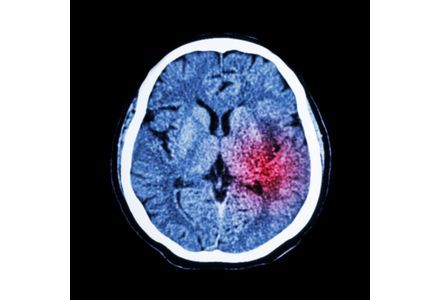

Tai biến mạch máu não là một bệnh lý xảy ra khi việc cung cấp máu lên một phần của não bị đột ngột ngừng trệ.

Tăng huyết áp, hút thuốc lá, đái đường, tăng lipid máu, một số bệnh tim (bệnh van tim, thiếu máu cơ tim, rung nhĩ), lạm dụng thức uống có cồn (rượu, bia)…. là những yếu tố nguy cơ của bệnh. Bệnh thường xảy ra đột ngột, tử vong cao và để lại di chứng nặng nề. Do đó, điều quan trọng là có hướng dự phòng sớm.